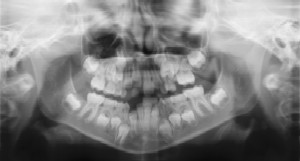

Dental Radiographs (X-Rays)

Radiographs (X-Rays) are a vital and necessary part of your child’s dental diagnostic process. Without them, certain dental conditions can and will be missed. Radiographs detect much more than cavities. For example, radiographs may be needed to survey erupting teeth, diagnose bone diseases, evaluate the results of an injury, or plan orthodontic treatment. Radiographs allow dentists to diagnose and treat health conditions that cannot be detected during a clinical examination. If dental problems are found and treated early, dental care is more comfortable for your child and more affordable for you.

The American Academy of Pediatric Dentistry recommends radiographs and examinations every six months for children with a high risk of tooth decay. On average, most pediatric dentists request radiographs approximately once a year. Approximately every 3 years, it is a good idea to obtain a complete set of radiographs, either a panoramic and bitewings or periapicals and bitewings. Pediatric dentists are particularly careful to minimize the exposure of their patients to radiation.

With contemporary safeguards, the amount of radiation received in a dental X-ray examination is extremely small. The risk is negligible. In fact, the dental radiographs represent a far smaller risk than an undetected and untreated dental problem. Lead body aprons and shields will protect your child. Today’s equipment filters out unnecessary x-rays and restricts the x-ray beam to the area of interest. High-speed film and proper shielding assure that your child receives a minimal amount of radiation exposure.